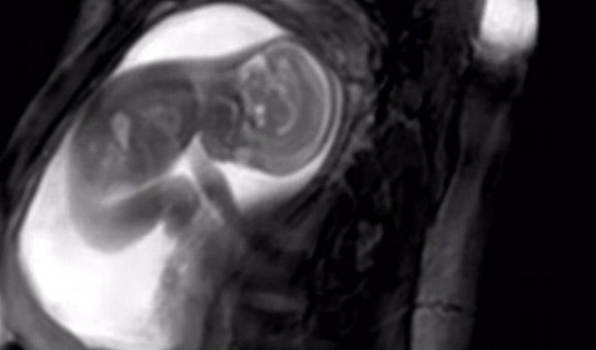

New MRI scan lets parents see their babies in AMAZING detail inside the womb

But while expectant parents up until now have had to be content with the rather grainy, sometimes hard-to-make-out-what-is-what ultrasound image (unless you private pay for the slightly more detailed 3D scan), soon parents-to-be could be able to watch their unborn bundles in a lot more detail thanks to a revolutionary new MRI scan.

The incredible detail reveals just how fully formed a foetus is at 20 weeks and has also now in the UK reignited the debate on lowering the current 24-week legal abortion limit in place.

In this short video, created by the iFIND project, you can see the scan of a 20-week-old baby – and learn exactly what they get up to while in utero.

To get a scan so to be so detailed, the researchers used algorithms, magnetic fields and radio waves, creating extra-high quality moving footage.

“Taking pictures of a 20-week fetus while they’re still in the womb really isn’t that easy,” Lloyd explains. “For one thing, they’re very small. The fetal heart, for example, with all of its tiny chambers and valves, is only about 15mm long: less than the size of penny.”